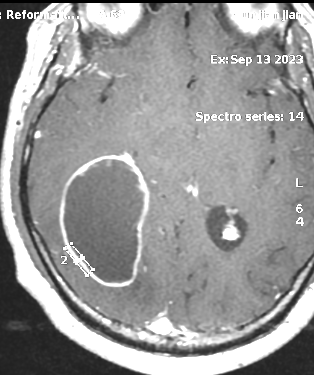

患者中年男性,因“颈部发紧、活动受限伴头晕近半月”入院。PE:NS(-)。头颅MRI平扫+增强检查示右颞枕叶椭圆形囊性肿物,边界清楚,信号均匀,病变周围可见片状水肿,中线结构略向左偏;增强扫描囊壁不规则环状强化(图1)。